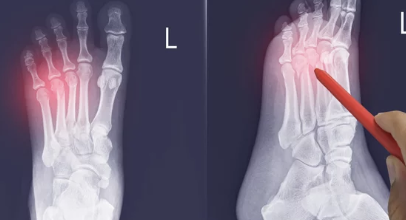

๋ฐ๊ฐ๋ฝ ๊ณจ์ ์ ์ธ๋ถ ์ถฉ๊ฒฉ์ผ๋ก ์ธํด ๋ฐ๊ฐ๋ฝ ๋ผ์ ๊ธ์ด ๊ฐ๊ฑฐ๋ ๋ถ๋ฌ์ง๋ ๊ฒ์ ๋งํฉ๋๋ค. ์ฃผ์ ์์ธ์ผ๋ก๋ ๋์, ๋ฌด๊ฑฐ์ด ๋ฌผ๊ฑด ๋จ์ด๋จ๋ฆผ, ๋ฐ ๋ฐํ, ์คํฌ์ธ ํ๋ ์ค ๋ถ์ ๋ฑ์ด ์์ต๋๋ค. ํนํ ๊ฒจ์ธ์ฒ ์๋ ๋นํ๊ธธ ๋์ ์ฌ๊ณ ๋ก ์ธํด ๋ฐ๊ฐ๋ฝ ๊ณจ์ ํ์๊ฐ ์ฆ๊ฐํ๋ ๊ฒฝํฅ์ด ์์ต๋๋ค.

2. ๋ฐ๊ฐ๋ฝ ๊ณจ์ , ์ด๋ค ์ฆ์์ด ๋ํ๋ ๊น์? ๐ค

- ์ฌํ ํต์ฆ: ๊ณจ์ ๋ถ์๋ฅผ ์์ง์ด๊ฑฐ๋ ์๋ ฅ์ ๊ฐํ๋ฉด ์ฌํ ํต์ฆ์ด ๋๊ปด์ง๋๋ค.

- ๋ถ๊ธฐ & ๋ฉ: ๊ณจ์ ๋ถ์ ์ฃผ๋ณ์ด ๋ถ๊ณ ๋ฉ์ด ๋ค ์ ์์ต๋๋ค.

- ๋ณํ: ๊ณจ์ ์ด ์ฌํ ๊ฒฝ์ฐ ๋ฐ๊ฐ๋ฝ ๋ชจ์์ด ๋ณํ๋ ์ ์์ต๋๋ค.